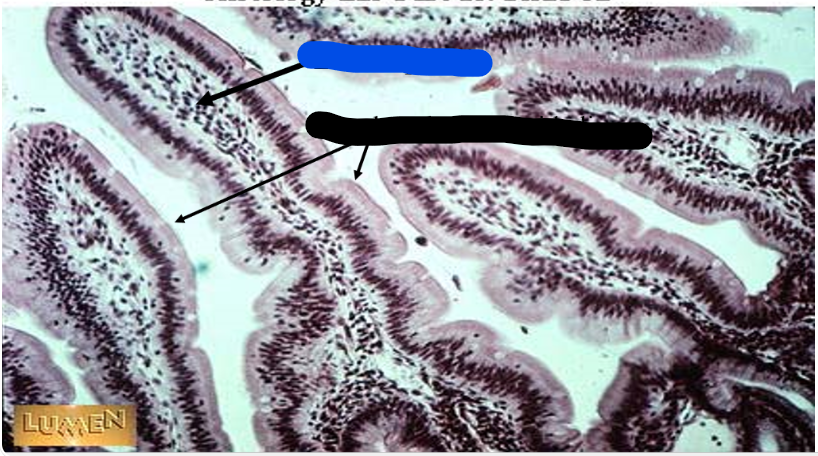

the arrows point to

brush border/microvilli

villi

the blue arrow

the red arrow

the black arrows

crypts

this is in the

jejunum